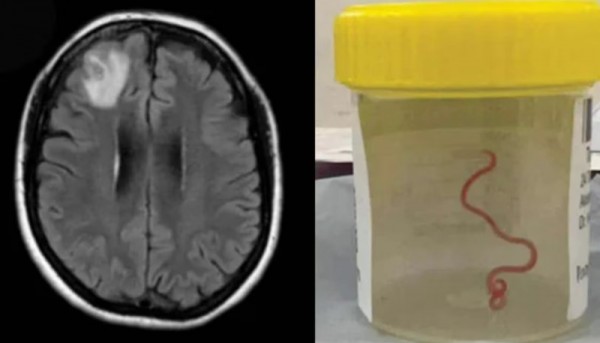

60대 호주 여성의 뇌에서 발견된 8cm 길이의 회충

2021년 1월 A씨는 복통과 설사, 마른 기침, 발열, 발한 등의 증상으로 지역 병원에 입원했지만, 그녀의 증상은 호전되지 않았고, 다음해에는 건망증과 우울증 증세까지 보였던 것으로 전해졌다. 결국 A씨는 큰 병원인 캔버라 병원으로 이송됐고, 자기공명영상장치(MRI) 검사를 진행한 결과 의료진은 수술이 필요한 이상 징후가 있다는 소견을 냈다. 하지만 이때까지도 의료진들은 그녀의 뇌에서 살아있는 회충이 발견될 것이라고는 생각지도 못했다고 한다. 신경외과 전문의가 회충이 있다는 사실을 처음 확인했고 "신경외과 의사들은 뇌 감염을 자주 다루긴 하지만, 이런 일은 일생에 한 번 있을까 말까한 일이다"라고 말했다. 캔버라 병원 의료진들은 회충의 종류에 대해 결론을 내리지 못하여 연방과학산업연구기구(CSIRO)의 도움을 구했고 회충의 정체가 '오피다스카리스 로베르시'라고 했다. 이는 주로 비단뱀에서 발견되는 회충으로, 인간에게서 발견된 것은 이번이 처음인 것으로 알려졌다. A씨는 비단뱀이 서식하는 호수 근처에 거주하는 것으로 알려졌고, 뱀을 직접적으로 만진 적은 없지만 종종 풀을 뜯어 요리해먹곤 했던 것으로 알려졌다.의료진은 비단뱀의 대변을 통해 나온 기생충이 풀에 묻었고, A씨가 이를 섭취하게 돼 감염됐을 가능성이 있다고 설명했다.